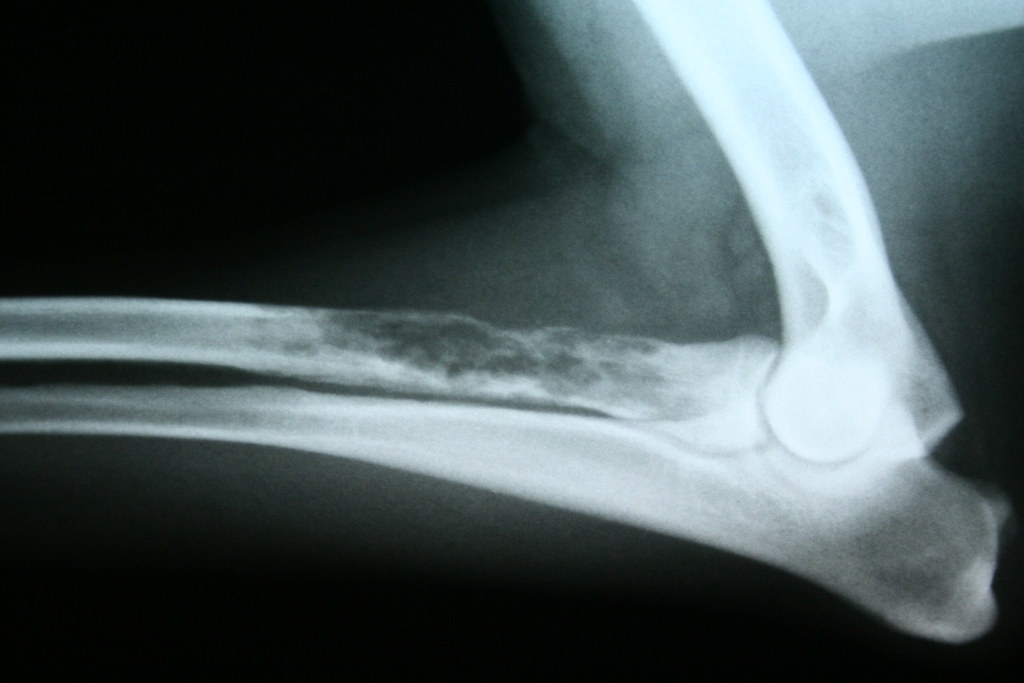

При диагностике остеосаркомы собак поражающей скелет, первым методом обследования является качественное радиографическое обследование животного.

Общие отклонения на снимках при остеосаркоме заключаются в почти полном лизисе кости в зоне поражения совместно с остеобластическими и остеокластическими изменениями различной степени выраженности на периферии. Радиографическими особенностями остеосаркомы кости являются выраженный лизис кортикального слоя (вплоть до патологических переломов), формирование новой кости вокруг опухоли (типа вспышки солнца) с приподнятием надкостницы и значительное увеличение объема окружающих мягких тканей. На ранних этапах развития опухоли, радиографические изменения могут заключаться в потере ясного трабекуллярного паттерна метафиза и размытии переходной зоны в месте локализации опухоли. Радиографические изменения остеосаркомы собак зависят от размера, гистологического подтипа, локализации и времени развития опухоли. Радиографические признаки остеосаркомы сходны с таковыми при остеомиелите, особенно грибковом. Радиографические изменения при остеосаркоме кошек сходны с таковыми при остеосаркоме собак.

При рентгенографическом исследовании можно увидеть патологический перелом, лизис кости, и другие признаки, по которым уже можно поставить предварительный диагноз.